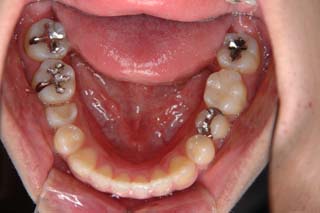

(叢生/顎関節症/上顎左側小臼歯抜歯)

左側の臼歯部干渉が、治療を通じてみられたので、オーバーコレクション気味に軽い臼歯部開咬にしてあります。咬合器上での顎位の偏位はかなり軽減し、頭頚部の症状も随分軽快したようです。歯列の改善と、顎関節症状には、なんだかの関連があると推測されますが、不明なことが多いです。